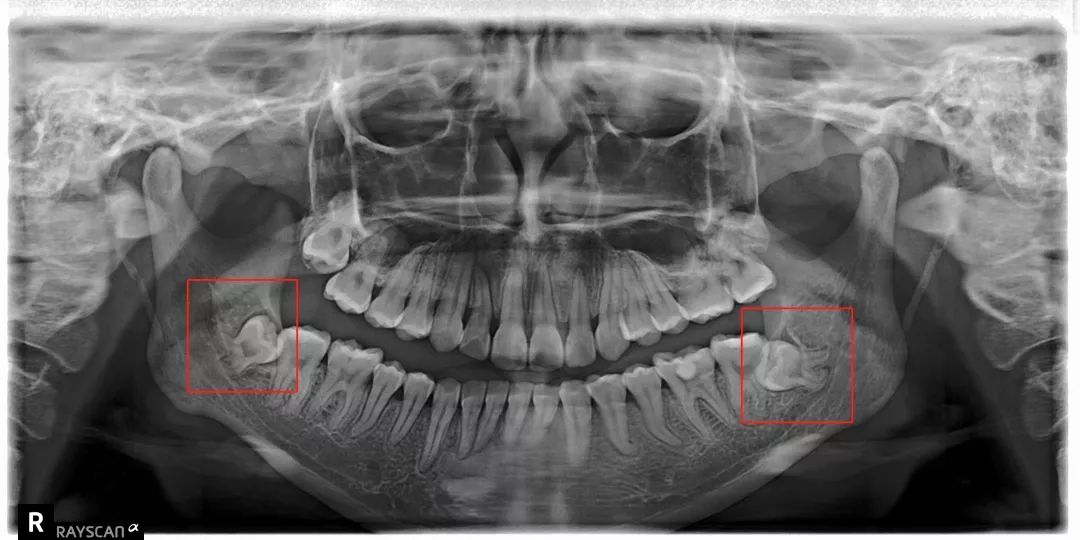

科普一波智齿~

把整副牙齿挤歪:

比方说像树根一样长出很多「根」

扎根在骨头里,死死抓住

还有一部分智齿长期发炎

可能会跟我们的骨头黏连